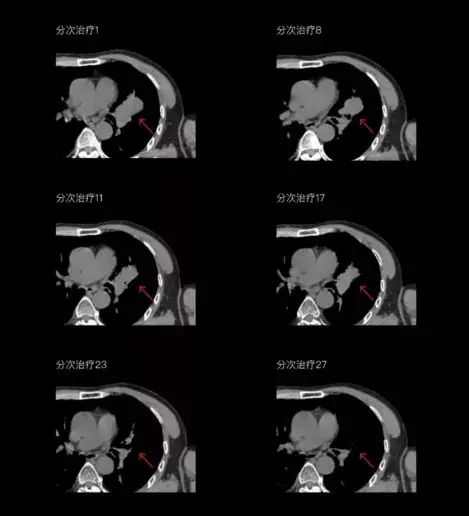

一體化CT-linac讓自適應(yīng)放療ART概念變?yōu)楝F(xiàn)實(shí)。患者全療程狀態(tài)監(jiān)控,適時(shí)在線調(diào)整治療計(jì)劃,精準(zhǔn)控制治療劑量,為患者動態(tài)定制個(gè)體化治療方案。uAI賦能智能勾畫和自動計(jì)劃,秒級勾勒靶區(qū)和危及器官,大幅縮短自適應(yīng)放療時(shí)間。

聯(lián)影CT-linac全程監(jiān)測治療過程病灶的變化,及時(shí)調(diào)整和優(yōu)化治療方案